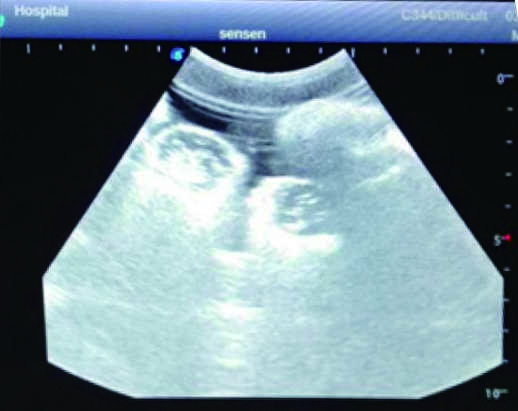

2) Real clinical ultrasound images with clear anatomical structures like intestines, part of the liver, arteries and veins, etc.

1) Ultrasound-guided puncture and abdominocentesis practice